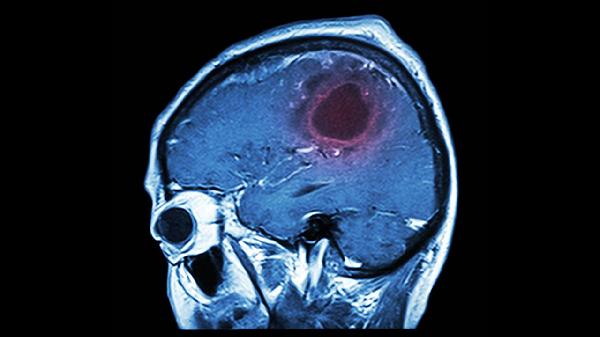

脑溢血发生的前几天,身体可能会发出这3个求助信号!千万别忽视

熬夜追剧时突然眼前发黑?起床后莫名头痛得像要裂开?这些看似平常的小症状,可能藏着危险的秘密。大脑这个精密仪器在罢工前,往往会提前拉响预警,只是我们常常误以为是疲劳或感冒的恶作剧。